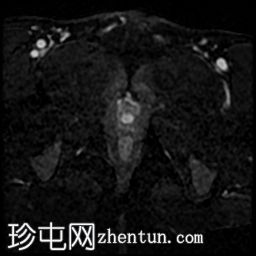

轴位

STIR序列

前列腺大小为32.8 x 41.5 x 34.7 mm(前后径 x 宽度 x 头尾径),体积为25.88 ml,属于正常范围。前列腺中央可见一逗号状囊性占位性病变,大小为17.3 x 12.1 x 9.3 mm(头尾径 x 前后径 x 宽度)。可见囊肿与前列腺尿道相通。囊内未见可疑内容物——具体而言,未见囊内出血或碎屑——弥散加权成像结果为阴性,提示无囊内感染。

本例为一例发生于青年人的单纯性逗号状中央型前列腺内囊肿。